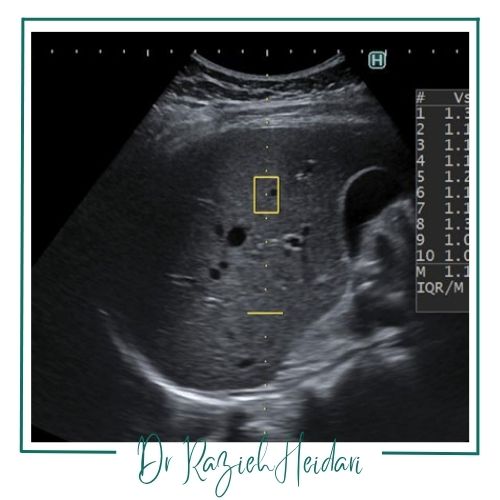

الاستوگرافی موج برشی: دستگاه موجهای برشی تولید میکند و سرعت عبور موج در بافت اندازهگیری میشود.

روند الاسیته پستان

تفسیر نتایج سنجش سفتی تودههای پستان

الگوهای نرم و یکنواخت بیشتر احتمال وجود ضایعات خوشخیم مثل کیستهاست.

الگوهای سفت و نامنظم نیازمند بررسی دقیقتر و گاهی نمونهبرداری هستند.

تفسیر مقادیر باید توسط رادیولوژیست و با توجه به سونوگرافی خاکستریاسکیل و سابقه بیمار انجام شود.